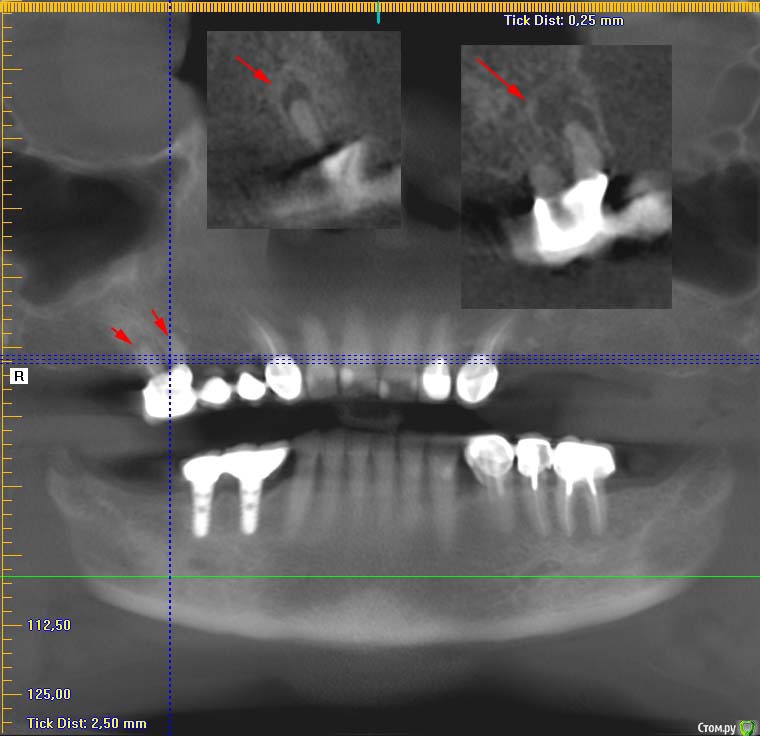

kozloff Опубликовано 27 марта, 2015 Поделиться Опубликовано 27 марта, 2015 (изменено) Если подразумевается зуб 24, то кисты нет, просто на панораме так выглядит особенность строения в/ч пазухи. Изменено 27 марта, 2015 пользователем kozloff Ссылка на комментарий

Endimi Опубликовано 27 марта, 2015 Автор Поделиться Опубликовано 27 марта, 2015 Если подразумевается зуб 24, то кисты нет, просто на панораме так выглядит особенность строения в/ч пазухи.Здравствуйте. Нет не 24, а задний верхний с левой стороны если смотреть на снимок. Ссылка на комментарий

kozloff Опубликовано 27 марта, 2015 Поделиться Опубликовано 27 марта, 2015 (изменено) Напишите мне в личку кого смотреть. Там несколько исследований у Вас на диске Если так, то да, есть Изменено 27 марта, 2015 пользователем kozloff 1 Ссылка на комментарий

Endimi Опубликовано 27 марта, 2015 Автор Поделиться Опубликовано 27 марта, 2015 Напишите мне в личку кого смотреть. Там несколько исследований у Вас на диске Если так, то да, естьВы все верно указали. Значит киста все таки есть=(Спасибо. Я Завтра Вам напишу. Ссылка на комментарий